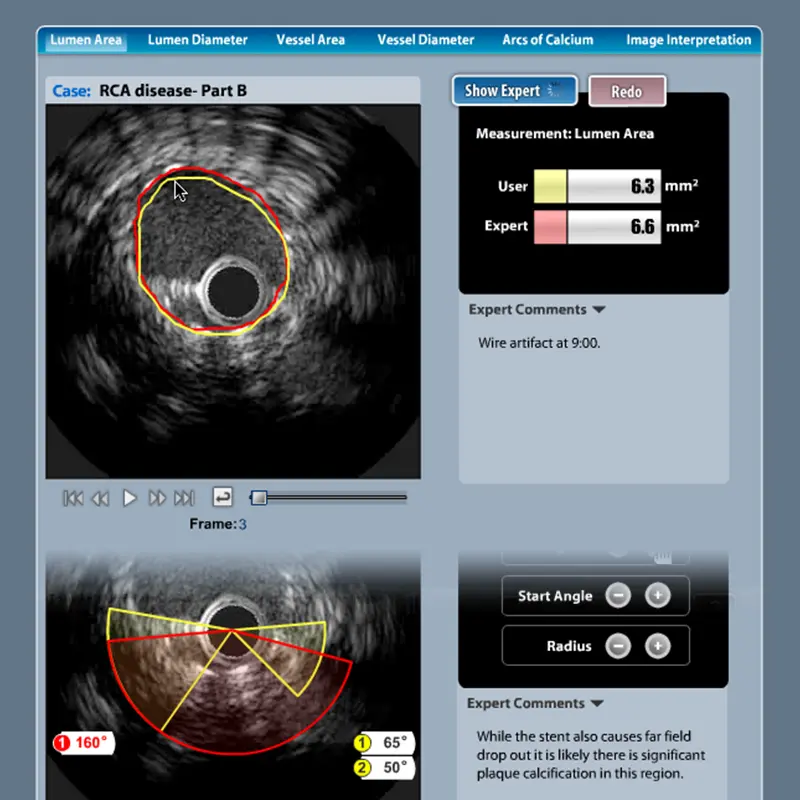

View the Case StudyThe Takeaway: Groundbreaking e-Learning apps that redefined a market, each winning an Adobe MAX Award (beating corporate behemoths like Toyota, Yahoo and TIAA-Cref), and delivered real-world simulation that helped cardiologists save lives.

View the Case StudySince 2003, thousands of projects have been submitted to Adobe for MAX Award consideration and winners include industry titans like Yahoo, Pepsi, T-Mobile, Nike, NASA, BMW, and eBay. Only three companies have won two awards: Yahoo, Interone Worldwide GmbH and Multiweb Communications. I am honored to have my work with Multiweb be in such impressive company. For both TeachIVUS and TeachCTA I was the primary architect, designer, and programmer.